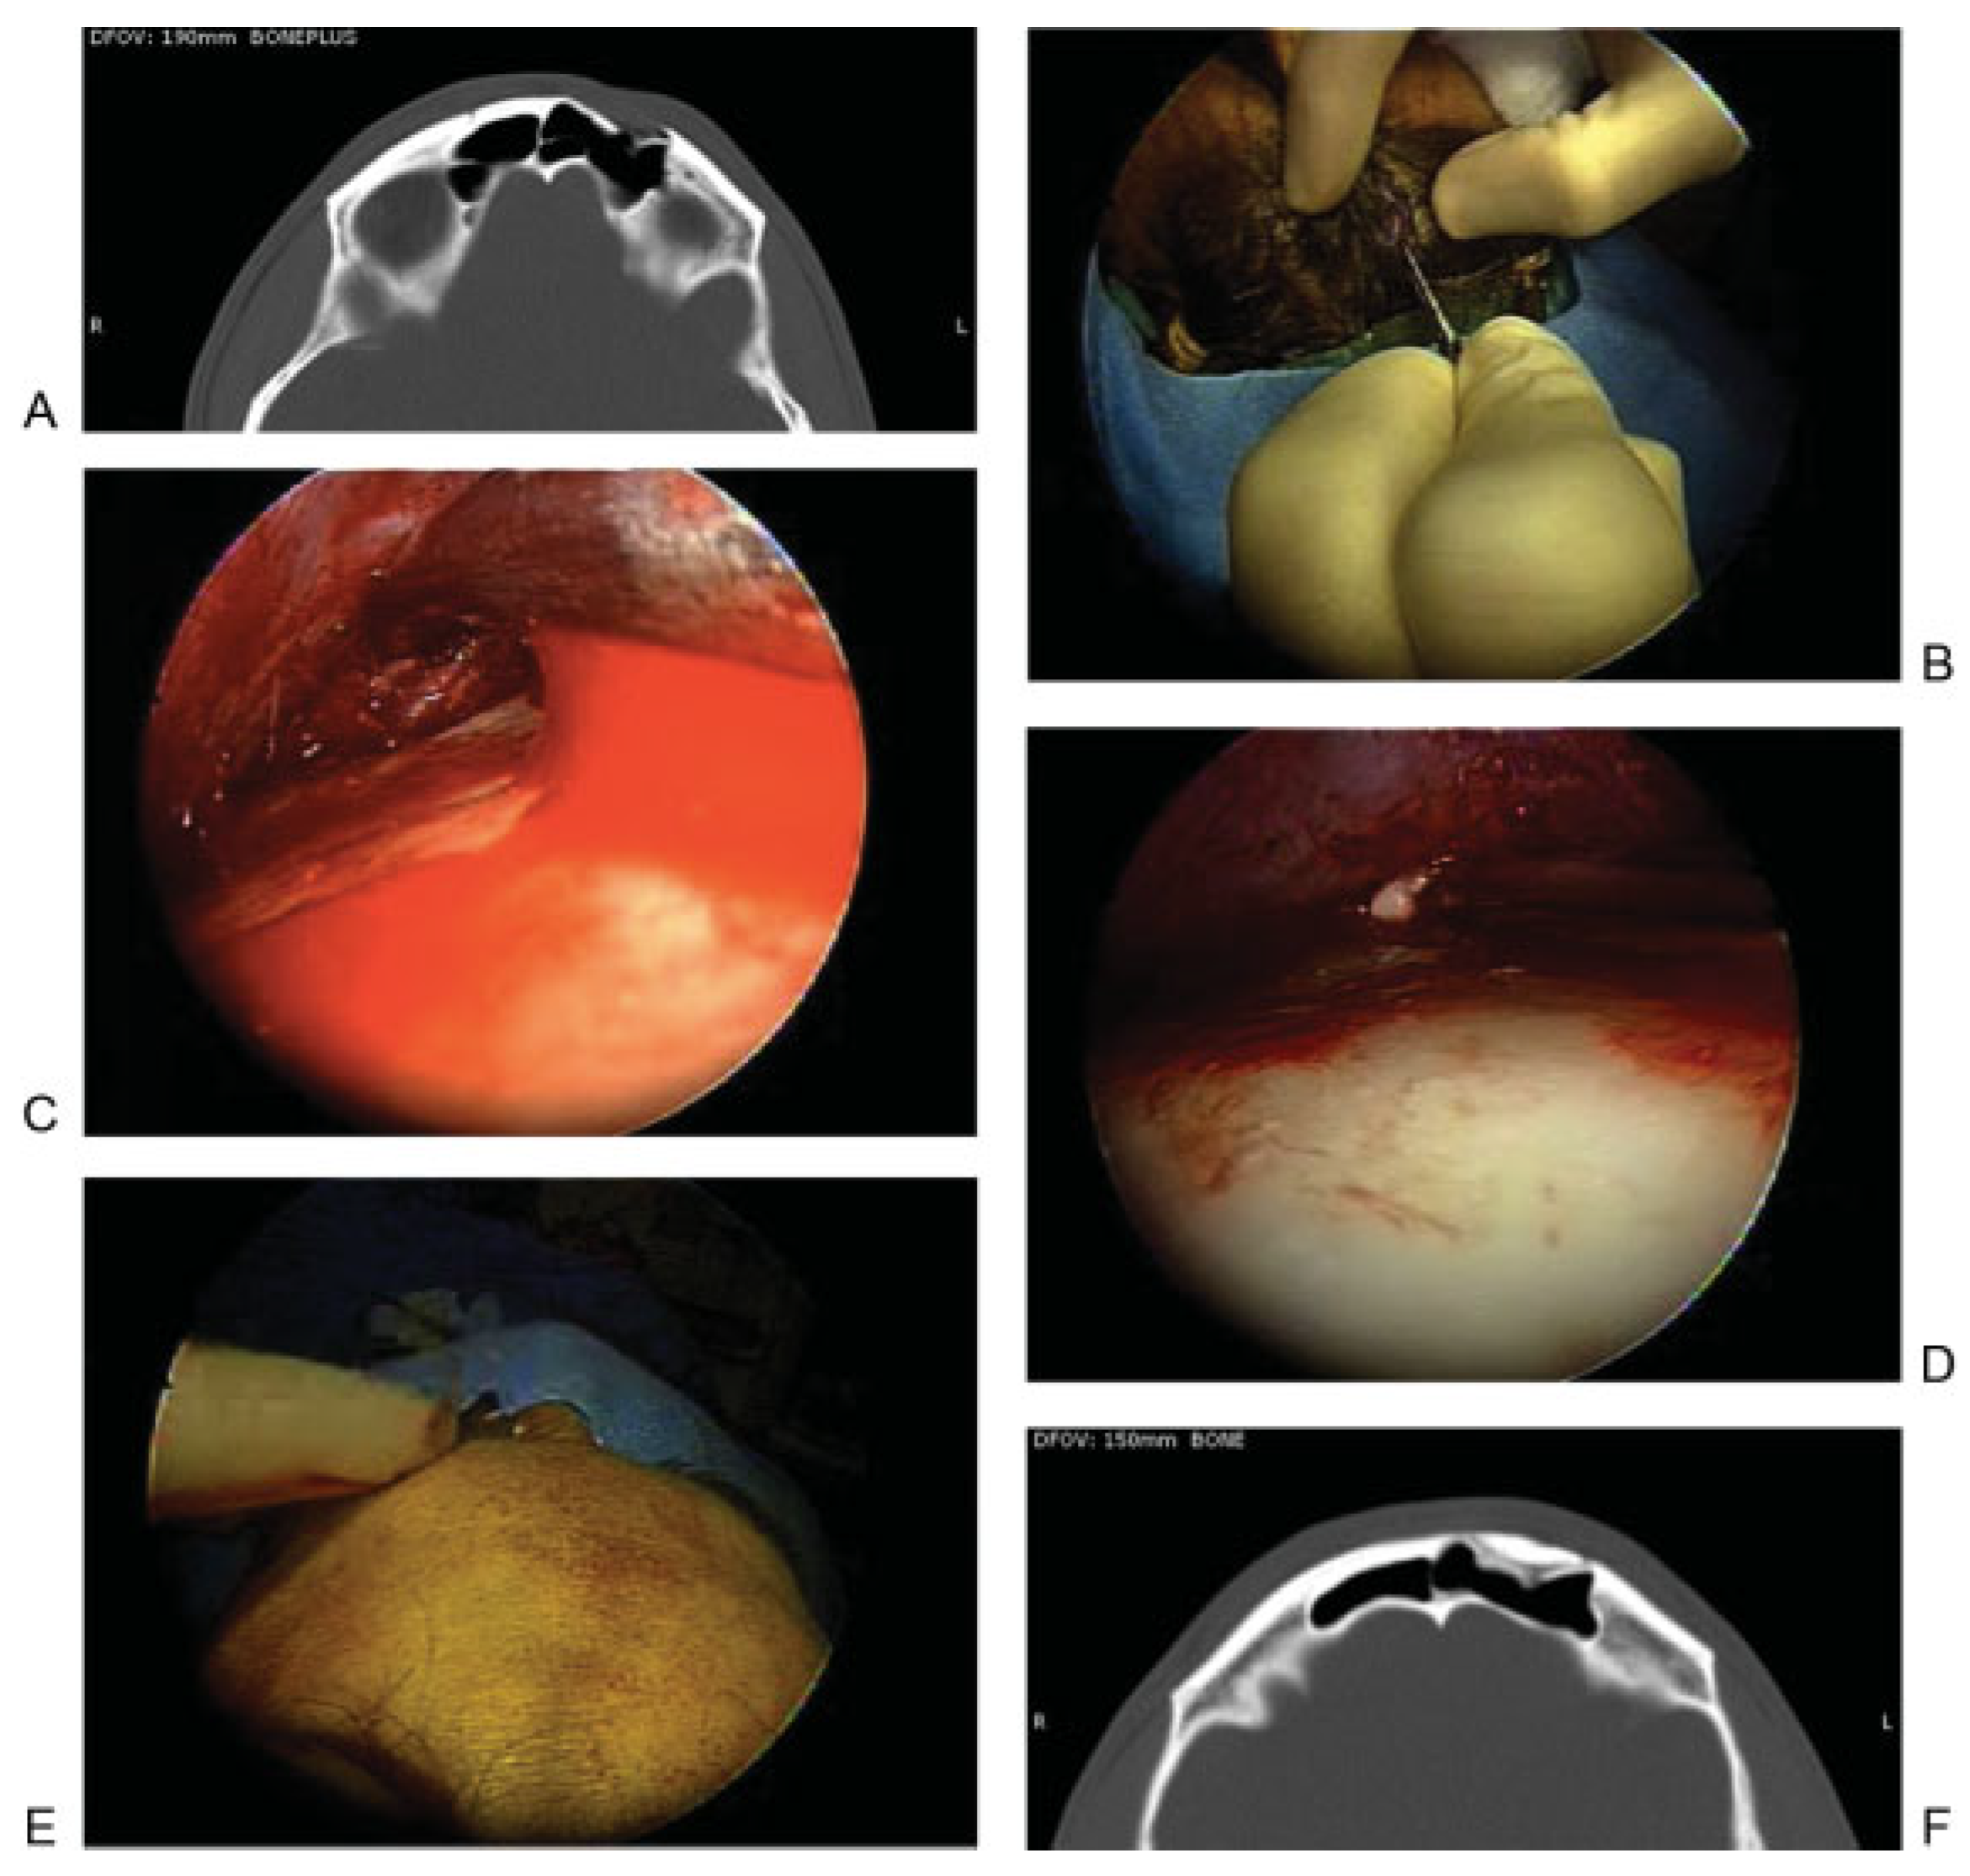

Figure 6 and Figure 7 illustrate cases in which trephination was used to repair posterior wall defects. Figure 6 demonstrates a situation in which the patient had active CSF rhinorrhea at the time of initial injury. Imaging studies demonstrated a fracture involving the posterior table of the frontal sinus, extending from the roof of the frontal sinus to the ethmoid skull base. The ethmoid portion of the defect was repaired using a graft by way of a transnasal endoscopic approach. However, the apex of the frontal sinus defect could not be reached in this way and was accessed through a frontal sinus trephination. Although there was not a large defect in the bone, there was an active CSF leak along the length of the fracture. The entirety of the defect was repaired with placement of a mucosal graft, and the trephination site was repaired using a small piece of titanium mesh. Postoperative imaging has shown a well aerated and healed frontal sinus, and endoscopic visualization has shown a patent frontal sinus outflow tract.

Figure 6.

(A, B) Axial and coronal computed tomographic (CT) images demonstrating a fracture involving the posterior table of the left frontal sinus. Fluid is also seen in the sinus. (C, D) Postoperative axial and coronal CT images demonstrating a well aerated and healed frontal sinus after use of a trephination for repair of the cerebrospinal fluid leak resulting from the defect. The axial image shows the titanium mesh used for reconstruction of the defect resulting from the entry into the frontal sinus.

Figure 7.

(A) Axial computed tomographic showing fractures of the posterior aspect of the right frontal sinus and the intersinus septum. A frontal sinus trephination approach was used to manage this defect. (B) Intraoperative picture showing a drill being used to perform the trephination and expose the frontal sinus lumen. (C) Endoscopic view of the frontal sinus lumen through the trephination shows a small area of brain herniation (black arrow) into the frontal sinus through the posterior table defect. Endoscopic visualization also shows a patent frontal sinus outflow tract (white arrow). (D) After encephalocele cauterization, repair was performed using a bone graft and mucosal graft. Image shows mucosal graft in place (black arrow) and that the frontal sinus outflow tract remains patent (white arrow).

The patient in Figure 7A did not have an active CSF leak at the time of initial injury. Imaging showed a fracture along the posterior frontal sinus wall. In the absence of a CSF leak, no acute exploration or repair was performed. The patient presented 2 years later with an episode of meningitis. Imaging revealed an encephalocele at the site of the previous posterior wall injury. The defect was repaired by way of a frontal sinus trephination approach, as shown in Figure 7B–D. In this case, the defect was repaired using bone and mucosal grafts while maintaining a patent frontal sinus outflow tract.